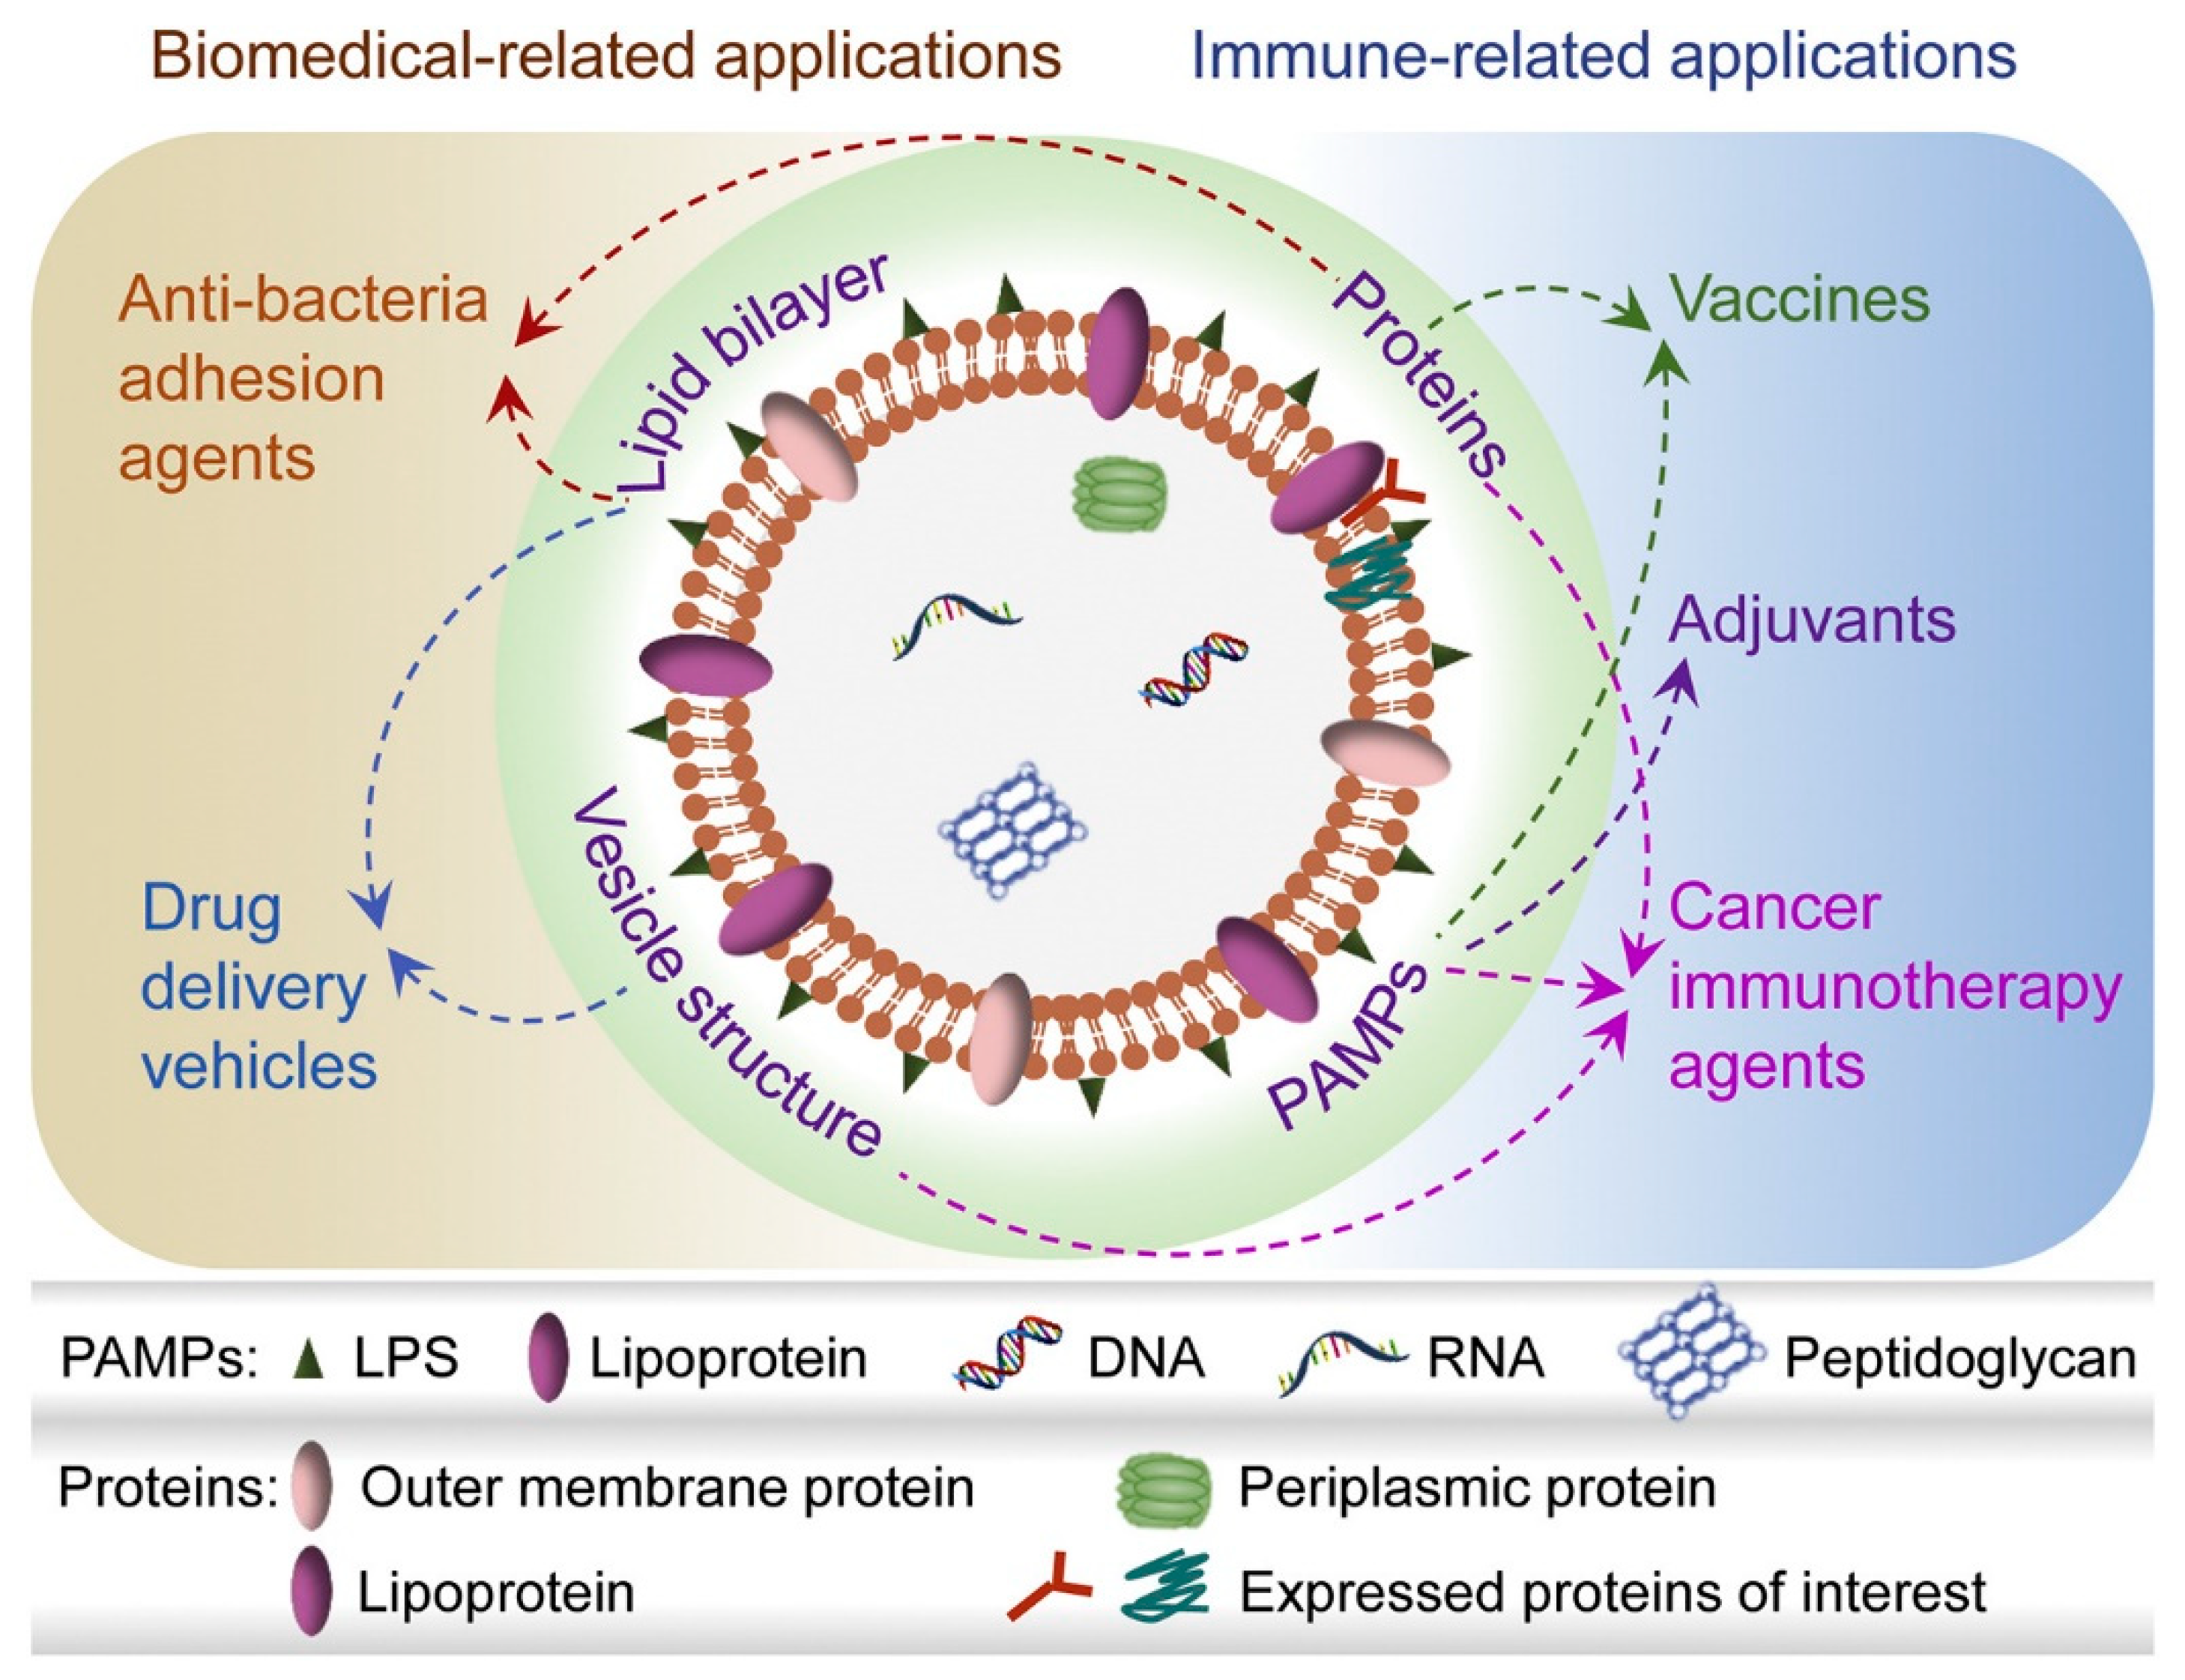

2. Vaccines and Nanovesicles

The Role of Gram-Negative and Positive Extracellular Vesicles in Vaccine Development

- Li, M.; Zhou, H.; Yang, C.; Wu, Y.; Zhou, X.; Liu, H.; Wang, Y. Bacterial Outer Membrane Vesicles as a Platform for Biomedical Applications: An Update. J. Control. Release 2020, 323, 253–268. [Google Scholar] [CrossRef] [PubMed]